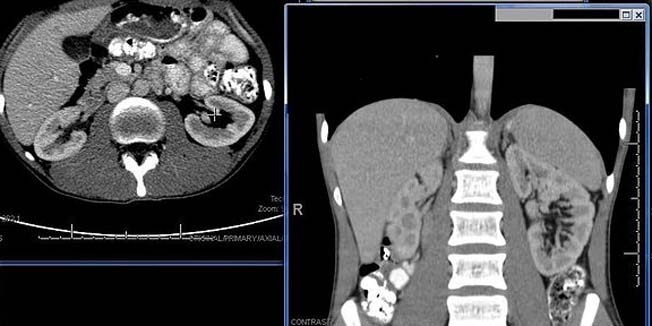

Liječnici će uskoro imati mogućnost da pacijentima uklanjaju bubrežne kamence u samo jednom postupku i to zahvaljujući razvijanju nove metode poznate pod nazivom bilateralna simultana uteroskopija. Tom bi se metodom oba bubrega mogla očistiti od kamenaca istodobno umjesto u dvije zasebne operacija kao što je to dosad bio slučaj. Postupak uključuje vizualizaciju i pozicioniranje kamenaca uz pomoć uteroskopa, a potom upotrebu lasera za njihovo razlamanje.

Bubrežni kamenci, od kojih pati oko 10 do 15 muškaraca te oko 2 do 7 posto žena nastaju kad se kristali soli akumuliraju u nakupine nalik kamenju koje tijelo ne može izlučiti. Takve nakupine mogu dovesti do zastoja u mokraćnom sustavu, uzrokovati jaku bol te učestale infekcije i sepse u mokraćnom traktu.